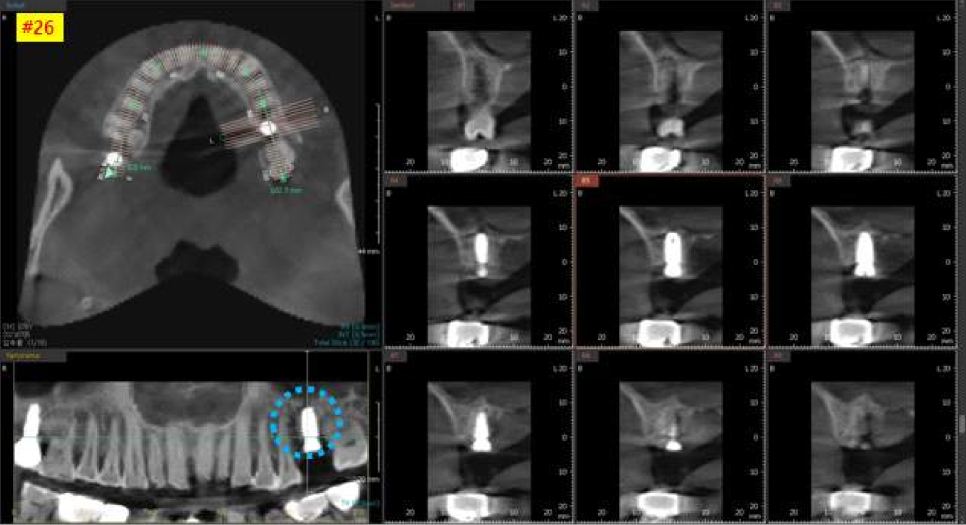

먼저 왼쪽 위 치아 수술을 먼저 진행했는데요,

파노라마 엑스레이랑 3차원 CT 사진을 보시면

아주 잘 심어진 상태를 보실 수 있습니다.

염증이 없는 상태여서, 뼈이식 없이 즉시 임플란트 식립을 진행 하였습니다.

수술 후, 초기고정력도 높게 잘 나왔습니다.

임플란트 실밥을 제거하고

한달 후에 초기고정은 잘 되고 있는지

문제가 생기지는 않았는지

체크를 하기 위해서 파노라마 엑스레이랑

3차원 CT사진 촬영을 진행했습니다.

엑스레이상으로도 눈으로 봤을 때도 치유가 잘 되고 좋은 상태였습니다.